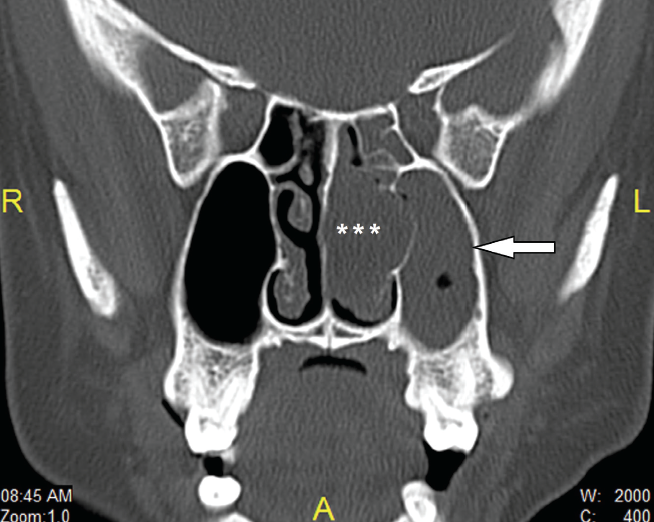

Michael Kaplan, DO, MC; Jeannette M. McIntyre, MD, LT, MC; James C. Higgins, DO

A 47-year-old African American female presents to her primary care physician with a 1- month history of a persistent swollen left lower lip.